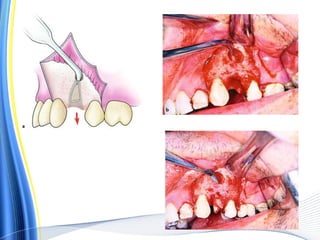

Steps in the surgical extraction of an intact

maxillary first molar. Reflection of the envelope flap,

sectioning of two buccal roots from the crown (a), removal

of the crown together with the palatal root, and then finally

removal of the mesial and distal roots (b)

An L-shaped incision is made and the flap is reflected.

The buccal plate covering the surface of the root is

removed, and the tooth is extracted using forceps

a, b. Surgical extraction of a mandibular

molar

with hypercementosis at the distal root tip.

The envelope

flap is reflected, part of the buccal plate is

removed, and the

tooth is sectioned buccolingually at the crown

as far as the

intraradicular bone

Extraction of the mesial portion of the tooth,

which includes the crown and root

Widening of the alveolus with a round bur, so

that removal of the root is possible without

fracturing the bulbous root tip